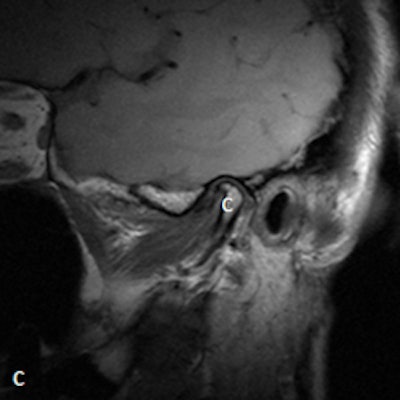

Dr. Friedman prefers that patients be supine on a stretcher with the jaw tilted away from the side to be examined. Then the person performing the ultrasound palpates the joint while the patient opens and closes her mouth. Gel is then placed on the joint, and the probe is placed at various positions around the joint. The images are examined to determine whether there is anterior displacement of the disk while the joint is the closed-mouth position.

"If the ultrasound is abnormal, the patient should be referred for an MRI, and any patient scheduled for surgery also must have an MRI," he said. "The main challenge is learning to detect what is normal on ultrasound. We also acknowledge that abnormal anteromedial and medially displaced disks may be missed or misinterpreted with ultrasound."